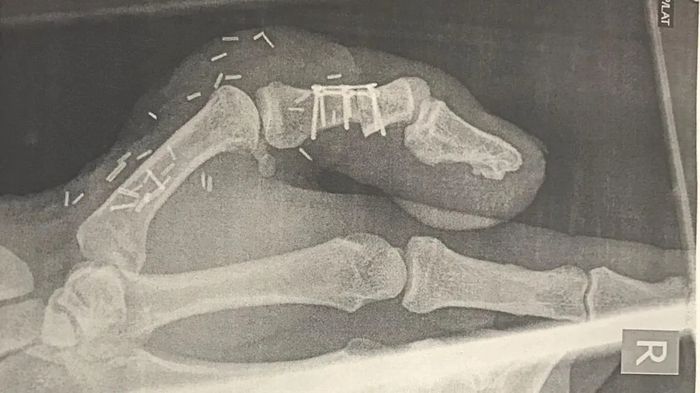

두 번째 선택지는 엄지발가락을 떼어내 엄지손가락에 붙이는 방법이었다. 리는 이 방법을 선택해 엄지손가락의 빈자리를 엄지발가락으로 메웠다.

리는 가위질과 악력 강화 같은 기본적인 동작을 다시 배워야 했지만 수개월간 물리치료를 받고 노력한 끝에 자신의 수선 가게로 돌아갈 수 있었다.

잠깐은 발가락을 붙인 손으로 돈을 건네는 것조차 부끄러워했다는 리는 “이제 붙인 엄지는 완전히 내 일부가 됐다. 더 이상 신경 쓰지 않는다”고 했다.